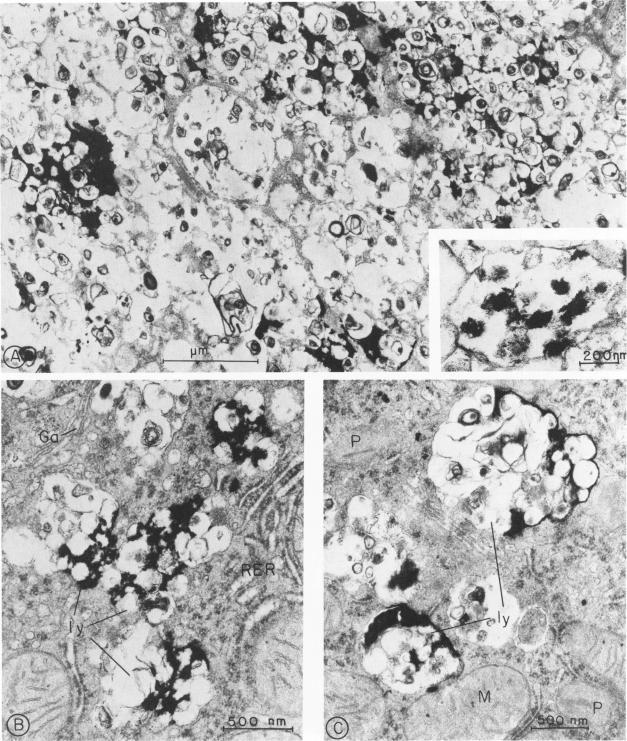

Electron-microscopic and cytochemical studies were carried out on tissues of NCTR-BALB/c mice. These mice are affected with a neurovisceral genetic disorder involving excessive tissue accumulation of lipid. Distinctive polymorphic intracellular inclusions, bounded by a membrane and containing lamellated bodies, were found in many cells of liver, spleen, lung, kidney, intestine, lymph nodes, and brain. The inclusions transformed reticuloendothelial cells into massive foam cells. Acid phosphatase cytochemical studies performed on sections of liver demonstrated that the inclusions were lysosomes. Fixation of liver in the presence of digitonin produced "spicules" in the inclusions characteristic of digitonin-cholesterol complexes. Clefts of cholesterol crystals were seen in the inclusions in liver, spleen, and lung. We conclude that the NCTR-BALB/c mice are affected by a lysosome lipid storage disease and that cholesterol is a major storage product.

对NCTR-BALB/c小鼠的组织进行了电子显微镜和细胞化学研究。这些小鼠患有一种神经内脏遗传性疾病,其特征是脂质在组织中过度积累。在肝脏、脾脏、肺、肾脏、肠道、淋巴结和大脑的许多细胞中发现了独特的多形性细胞内包涵体,这些包涵体有膜包裹并含有板层小体。这些包涵体将网状内皮细胞转化为大量泡沫细胞。对肝脏切片进行的酸性磷酸酶细胞化学研究表明,这些包涵体是溶酶体。在洋地黄皂苷存在的情况下固定肝脏,会在包涵体中产生洋地黄皂苷-胆固醇复合物特有的“针状物”。在肝脏、脾脏和肺的包涵体中可见胆固醇晶体的裂隙。我们得出结论,NCTR-BALB/c小鼠患有溶酶体脂质贮积病,胆固醇是主要的贮积产物。